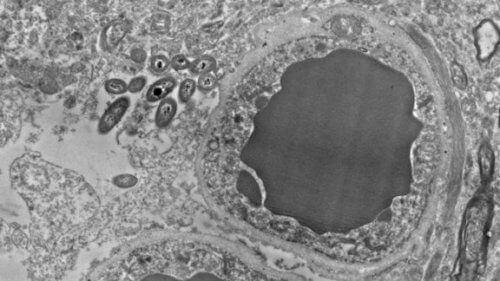

Titelbild mit freundlicher Genehmigung von Rosalinda Roberts, Courtney Walker und Charlene Farmer.

Dr. Rosalinda Roberts und ihr Team von der Abteilung für Psychiatrie und Verhaltensneurobiologie an der Universität von Alabama in Birmingham sind zu dieser neuen Erkenntnis gelangt.

Sie untersuchten die Gehirne von 34 verstorbenen Menschen. Die Hälfte der Personen war gesund gewesen, der Rest hatte an Schizophrenie gelitten. Darüber hinaus führten sie eine Parallelstudie mit Mäusen durch, um auszuschließen, dass die Bakterien erst post mortem auftraten oder eine Kontamination zu Fehlern führte.

In beiden Studien beobachteten die Wissenschaftler das Vorhandensein von Darmbakterien im Gehirn von Menschen und Mäusen in nicht infektiösen oder traumatischen Situationen.

Tatsächlich fanden die Forscher diese Bakterien in verschiedenen Bereichen des Gehirns. Hauptsächlich in der Substantia nigra, im Hippocampus, im präfrontalen Cortex und in geringerer Anzahl in weiteren Gehirnarealen. Außerdem zeigte keines der untersuchten Gehirne eine Entzündungserscheinung.